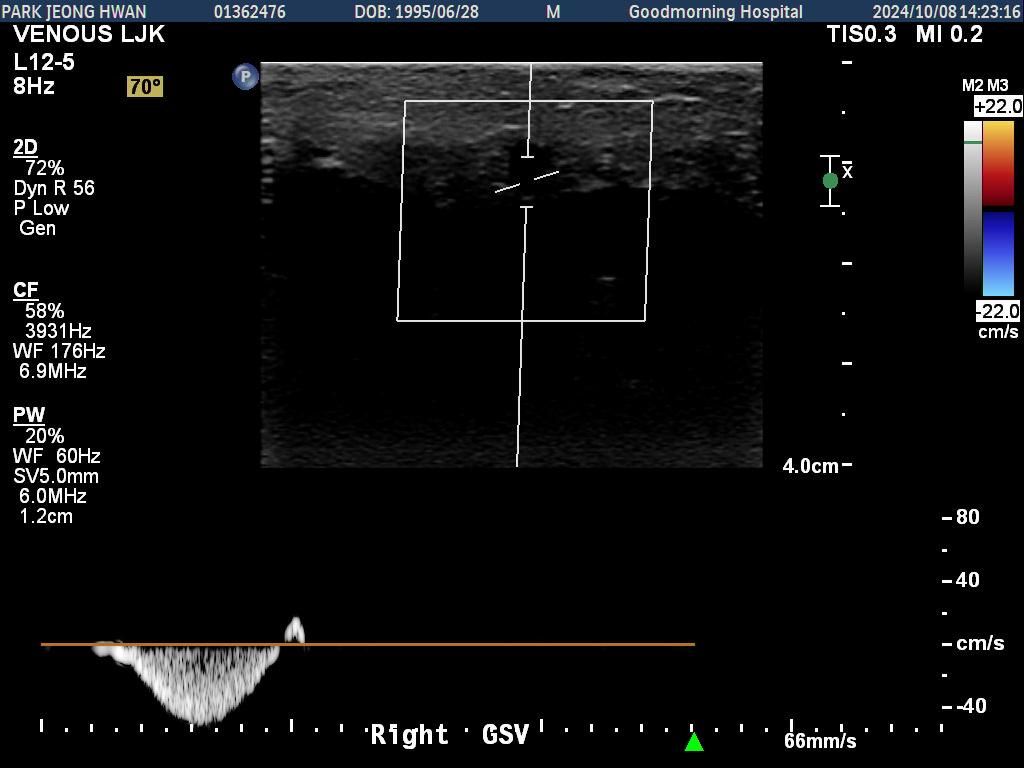

오른쪽 다리만 찍은 거구요. 종아리에서 사타구니까지 부분별로 찍었습니다.......................

• 1번 째 사진

• 2번 째 사진

• 3번 째 사진

• 4번 째 사진

• 5번 째 사진

• 6번 째 사진

• 7번 째 사진